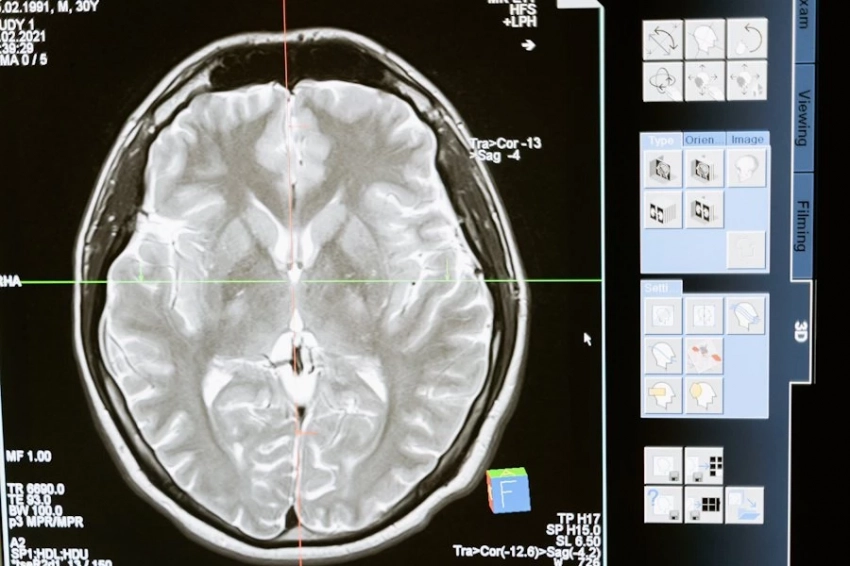

Спинной мозг является ключевым элементом центральной нервной системы. Он служит обеспечению передачи двигательных импульсов, а также сенсорной информации. Ученые поясняют, что через него открывается возможность влияния на различные структуры организма.